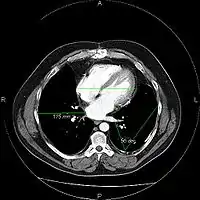

The same image following contrast adjustment, sharpening and measurement tags added by the system

A chest image displayed via a PACS